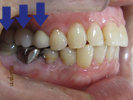

60代男性

右上に入れ歯を作ったが噛めず右で食事できないため来院。

2本インプラントをしました。

手前の銀色のかぶせも白いかぶせにかえました。

食事しやすくなったと喜ばれました。

治療前 |

治療後 |